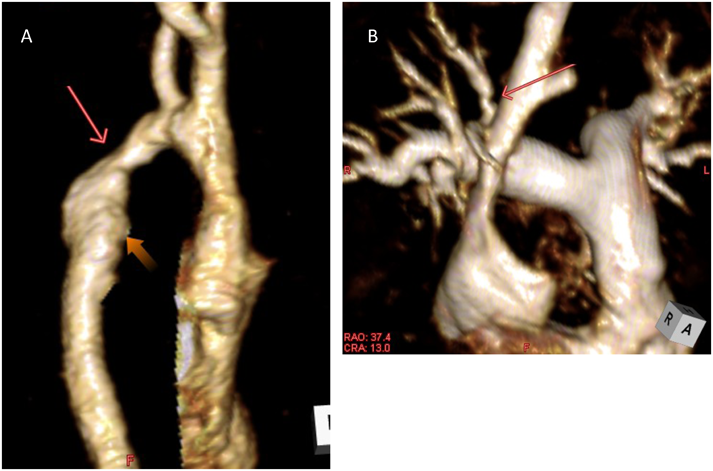

⑦造影3D MRA

ガドリニウム造影剤を静脈投与しながらSpoiled gradient echo pulseシーケンスを用いて撮影する.造影剤を用いると血液と周囲組織のコントラストが増大し,非造影では低信号となりがちであった流れの止まらない部位(modified BT shuntや肺静脈など)も明瞭に描出される(Fig. 1352–57).ただ,空間分解能はそれほど高くないので小児の冠動脈等の描出は難しい.空間分解能を上げると撮影に時間がかかり,目的とする部位に造影剤の濃淡を生じてしまう.

Pediatric Cardiology and Cardiac Surgery 32(4): 291-306 (2016)

Fig. 13 Contrast enhanced three-dimensional magnetic resonance angiography

A: Three-dimensional (3D) contrast-enhanced MRA of post subclavian flap operation. Red arrow: restenosis of aortic arch; orange arrow: aneurysm by recoarctation jet. B: 3D contrast-enhanced MRA of a patient with chronic thromboembolic pulmonary hypertension. Showing stenosis of the upper branch of right pulmonary artery. MRA: magnetic resonance angiography.